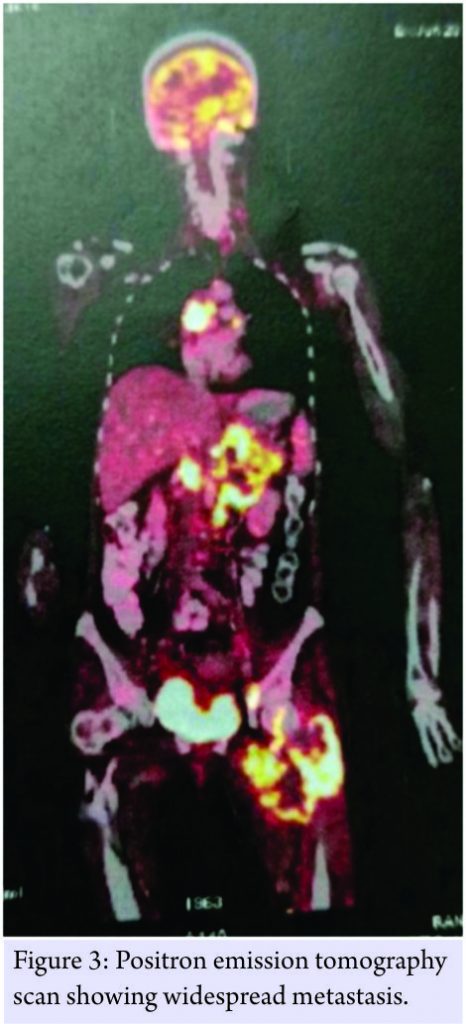

Contrast enhanced computed tomography (CECT) scan of chest and abdomen was done, that showed heterogeneously enhancing mass lesion in the right lung with peripheral consolidation and retroperitoneal, mesenteric, and hilar lymph nodes enlargement. Suprarenal deposits were also seen. Positron emission tomography scan showed lytic lesion with widespread metastasis as well (Fig. 3).